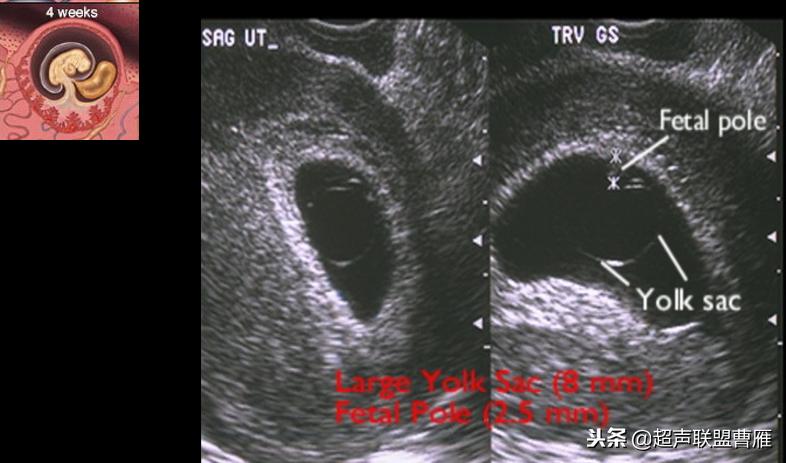

孕龄5.8周,胚极2.5mm,卵黄囊8mm,死胎

· 卵黄囊过大:有可能容易导致胎儿畸形(与不良妊娠结局有关)

· 卵黄囊过小:有可能自然流产或难免流产(与流产有关)

卵黄囊的大小与形态异常与胚胎的发育是否正常关系密切。卵黄囊增大,直径超过6.1cm,胚胎的预后不良。